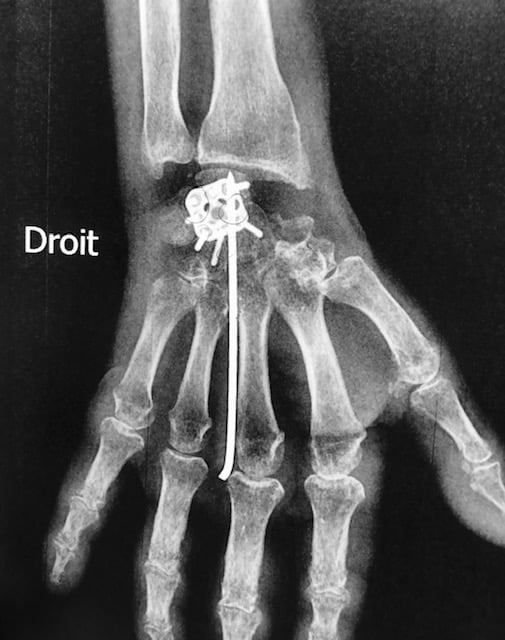

Fracture de l'extrémité du radius

Radio post opératoire - plaque de radius

Mise en place d’une petite plaque dite à vis verrouillée qui stabilise la fracture et autorise une reprise précoce de la fonction par de petits mouvements.

Intervention réalisée sous anesthésie locale et en ambulatoire. Elle consiste en une courte incision au niveau du poignet.